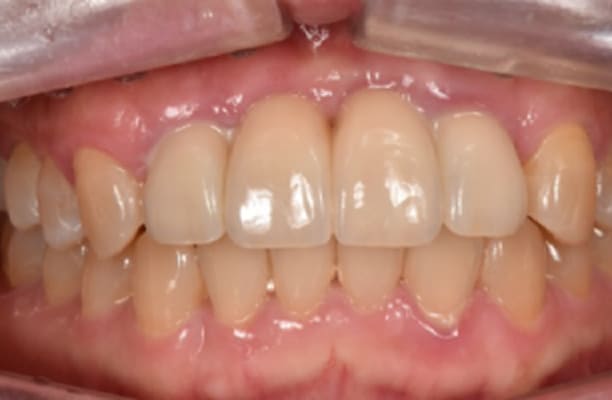

13+ 年

-

种植体植入 2012年10月 -

最终修复体 2013年1月 -

随访:13年 2025年3月